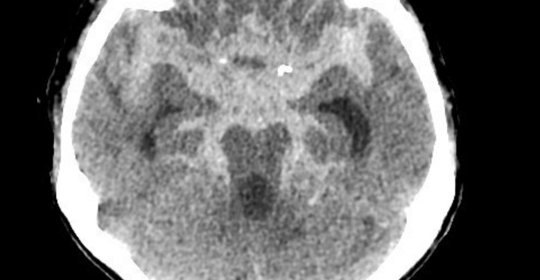

兒童血鉛超標:診斷與預防措施

兒童血鉛超標:血紅素濃度評估與管理